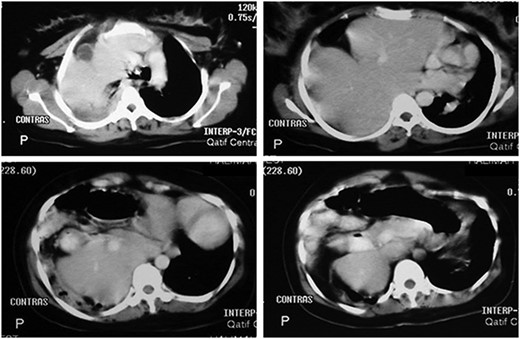

Chest x-ray (on arrival) showing a homogeneous opacity (the liver) occupying the right hemi-thorax with some bowel loops the right hemi-thorax with obvious mediastinal shift to the left side.

Her routine laboratory investigations including white cell count were normal. Electrocardiogram showed sinus tachycardia. Chest x-ray showed homogeneous opacity occupying the right hemi-thorax, and bowel loops were seen above the right chest with obvious mediastinal shift to the left side (Fig. 1). Abdominal computed tomography (CT) scan with contrast